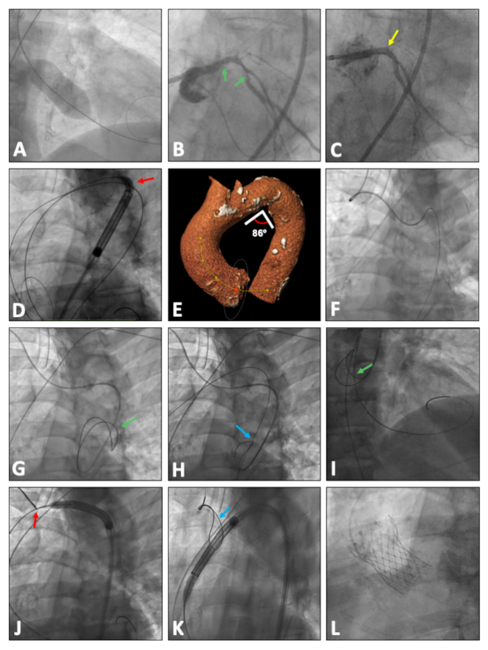

An 83-year-old man with symptomatic severe aortic valve stenosis with severe ventricular dysfunction underwent valvuloplasty with a 25-mm NuCLEUS-X balloon (B. Braun Interventional Systems) (Figure A) and percutaneous coronary intervention of the left main and circumflex arteries (left anterior descending artery presented a chronic total occlusion without viability of this territory) (Figure B and C) before being referred for transcatheter aortic valve replacement.

Through right femoral access, a high-support Lunderquist guidewire (Cook Medical) was placed into the left ventricle. An unsuccessful attempt was made to advance a 34-mm Evolut PRO+ valve (Medtronic) through the aortic arch due to a sharp angulation of the aortic arch distal to the origin of the left subclavian artery (Figure D and E). The crossing was not possible despite advancing an additional high-support guidewire (Safari2; Boston Scientific) from the left femoral artery to the aortic valvular plane with the intention of rectifying the angulation simulating the buddy-wire technique.

Through the right radial artery, a pigtail catheter was advanced over an angled Radiofocus guidewire (Terumo) to the descending thoracic aorta (Figure F). The pigtail catheter was exchanged for a Judkins Right (JR) 4, 6-French (Fr) guiding catheter. An Exeter Snare ES-35mm (AndraTec GmbH) was deployed in the descending thoracic aorta through the JR 4 catheter (Figure G; Video). A 0.032-inch guidewire was advanced from the right femoral access and passed inside the deployed snare (Figure H). With an Amplatz Left (AL) 1 catheter also passed inside the snare, the aortic valve was crossed with a straight guidewire. The high-support Lunderquist guidewire was positioned in the left ventricle crossing through the snare (Figure I). The bioprosthesis was advanced to the area of maximum angulation of the aortic arch. The snare was positioned at the level of the proximal portion of the aortic arch. Performing continuous traction with the snare on the high-support guidewire, coaxialization of the whole system was achieved, allowing it to advance through the area of maximum angulation (Figure J). Then the snare was released and withdrawn toward the distal portion of the aortic arch (Figure K). The 34-mm Evolut PRO+ valve was deployed successfully (Figure L). Once the bioprosthesis was released from the delivery system, the snare was inserted into the JR 4, 6-Fr guiding catheter and pulled out through the right radial artery.